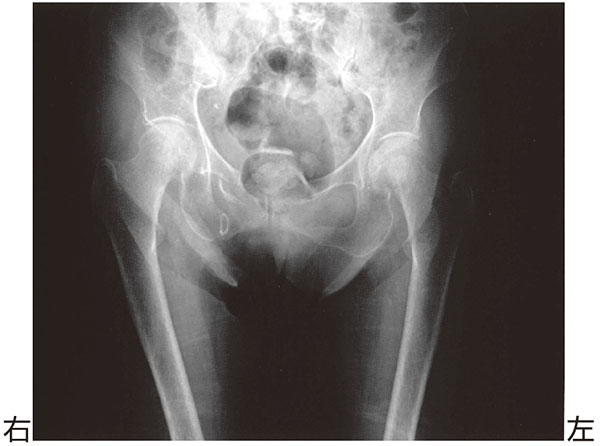

83歳の女性.転倒して右股関節痛を訴えた.エックス線写真を下に示す.

- 1.股関節脱臼

- 2.大腿骨近位部骨折

- 3.恥骨結合離開

- 4.恥骨骨折

- 5.腸骨骨折

解答: 4